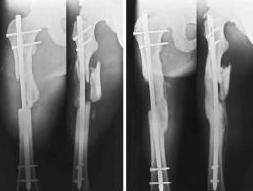

Кроме того, есть рекомендации АО ("Принцип био-

логичного остеосинтеза заключается в минимизации ущерба биологии вследствие хирургического вмешательства и контакта с имплантатом. Это достигается за счет менее точной репозиции и менее

жесткой фиксации")и картинки в ряде классических руководств (вложеннный рисунок)